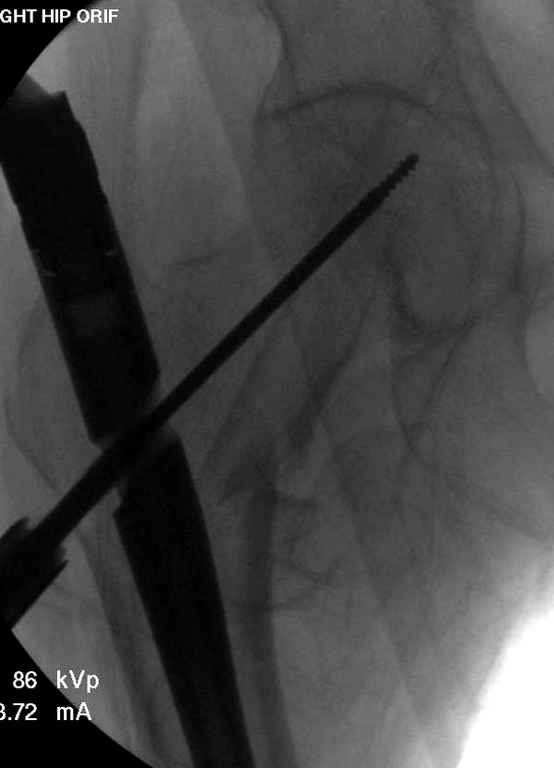

Re: Чрезвертельный перелом бедра

До выхода блокируемых гвоздей для фиксации косых подвертельных переломов в основном применяли Blade Plate. За счет уникальной конструкции создавался Fixed Angled Device, который соединял головку с диафизом, минуя зону перелома.

За счет особой конструкции клинка и подпорки (buttress) в диафиз создавалась стабильность, и предупреждалось скольжение по линии перелома. Перпендикулярная поверхность клинка предупреждала сгибательные и разгибательные смещения, и в сравнении с круглым винтом редко происходило прорезыванием.

Первые реконструкционные гвозди без блокировки винтов не смогли повторить преимущества, и из-за Z эффекта винтов происходило быстрое расшатывание.

С приходом менее агрессивных блокируемых цефаломедуллярных гвоздей (Gamma 3 и другие) изменилась тактика лечения. Несмотря на то, что вся стабильность держится вокруг одного блокирующего винта, в большинстве случаев гвозди приводили к успеху.

Вашему вниманию представляется похожий случай, пациентке 70, осложнился в течение одного месяца после операции. Ревизия с заменой сустава, кабельная фиксация на трохантер. При установке в дистальном диафизе обнаружен тонкий кортикальный слой и сделана профилактика от возможного перелома аллографтом.